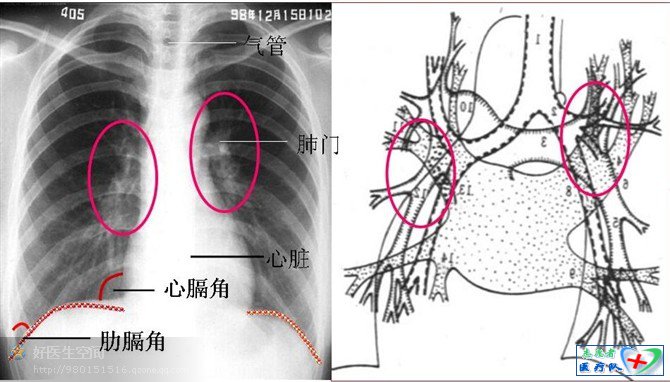

C(Cardiac)心脏、纵隔、肺门

心脏后对五到八胸椎,前对二到六肋骨。我们在读片的时候经常听到有一个概念叫“主动脉结”,它是什么意思呢?在哪里呢?主动脉结就是主动脉弓由右转向左出突出于胸骨左缘的地方,它平对左胸第二肋软骨。这里我还想说一点,那就是肺动脉段的位置,肺动脉段位于主动脉结下方,对判断肺动脉高压很有意义。心影的最外缘在膈平面以上称心尖上翘,代表右心室肥厚;反之心影的最外缘在膈平面以下称心尖下移,代表左心室肥厚。关于侧位片:心前三角变小则右心室大;心后三角大则左心室大。

纵隔阴影位于胸腔的中部,两肺之间,为软组织的阴影,主要器官有心脏、大血管、气管、支气管、食管及淋巴等。纵隔为前后径长的器官,一般在侧位上不易辨认其阴影位置。正位胸片上,上四分之一为气管与食管阴影,所以上纵隔较狭窄,两侧胸锁间隙相等,如一侧变窄或消失,则为体位该侧前斜,下四分之三主要为大血管和心脏阴影。心脏右缘上部为上腔静脉和升主动脉组成的突起为第一弓,第二弓为右心房;左缘自上向下主动脉弓为第一弓,肺动脉段为第二弓,左心耳为较小的第三弓,左心室为第四弓。当纵隔、心脏出现病变时,纵隔阴影增大,突起增多,或局部密度增高。由于心脏阴影占纵隔阴影比例较大,常遮盖肺后部与纵隔内的病变,所以怀疑纵隔病变,一定注意拍摄一张侧位胸片,区分病变部位。在侧位上不能显示纵隔上口大下口小,但可以清楚看到心脏、大血管和气管。心脏和大血管位于纵隔内,气管自前上方向后下方插入纵隔,各肺叶、段支气管亦可显示。纵隔分区较正位明显,可以分为上、中、下和后纵隔四个部分。当纵隔发生淋巴结肿大或肿瘤时,侧位可以较好的显示,纵隔增宽侧位不能显示。

肺门前方平第二到四肋间隙,后平对四到六胸椎棘突高度,在后正中线与肩胛骨内侧缘连线中点的垂直线上。肺门是血管、气管和淋巴管出入的地方,形成团块状密度增高的阴影,向外密度逐渐变淡,一般不超过内带。肺门有固定的形态,左肺门比右肺门高1~2cm,血管粗细均称。